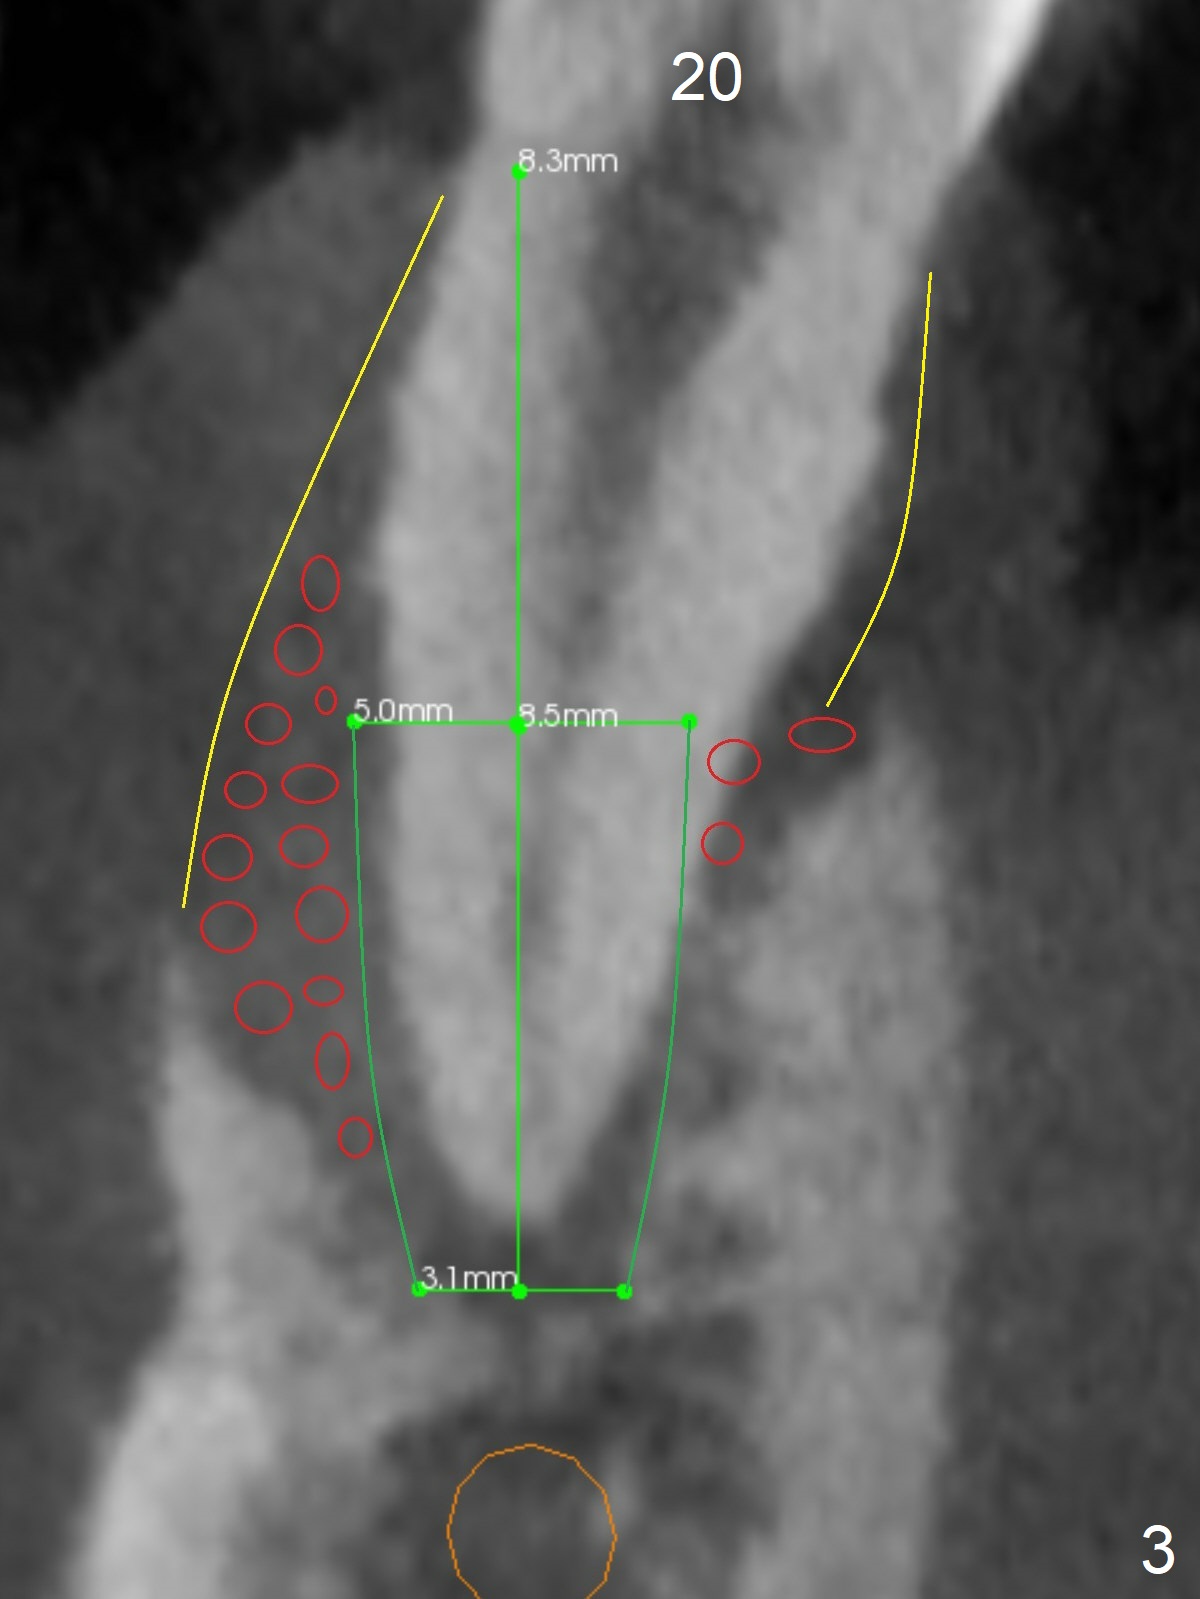

A 36-year-old man develops periodontal abscess at #19 and 20 after scaling & root planing. Since the site of #20 is close to the Mental Nerve, 3.8 mm tap or dummy implant will be used to form osteotomy instead of drills (Fig.1,3). While an implant will be placed in the middle of the socket #20, an implant will be placed as buccal as possible at #19 (Fig.4). If primary stability at #20 is poor, extract the tooth #21 and place a 3.8x10 mm lingually (Fig.2). PRF membrane will be placed prior to bone graft after implant placement (Fig.3 yellow).